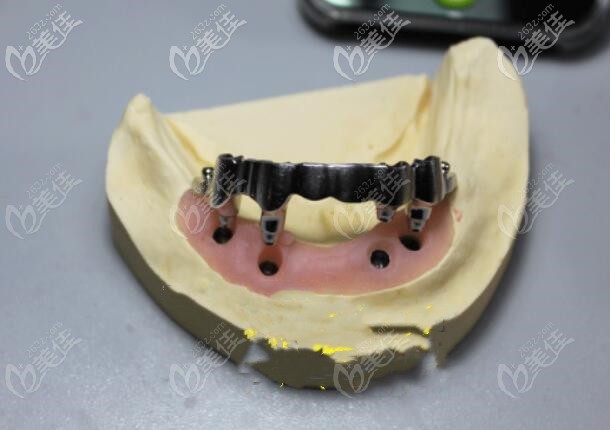

桿卡半固定種植牙▼

桿卡半固定種植牙

球帽半固定種植牙,也叫球帽覆蓋義齒▼

球帽半固定種植牙,也叫球帽覆蓋義齒